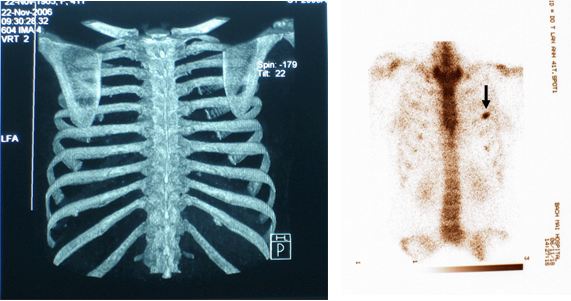

BN được chỉ định làm xạ hình xương toàn thân để kiểm tra tổng thể toàn bộ hệ thống xương, phát hiện ổ di căn xương sườn số 4 trái.

Ung thư đại tràng di căn xương

CT (-), Xạ hình xương với SPECT, Tc 99m- MDP (+)

Bàn luận: Trong điều trị ung thư việc xác định đúng giai đoạn bệnh có ý nghĩa quyết định phương pháp điều trị, từ đó mang lại hiệu quả điều trị tốt nhất cho người bệnh. Nếu chỉ dùng các phương pháp chẩn đoán thông thường rất dễ bỏ sót tổn thương qua đó đánh giá không đúng giai đoạn bệnh. Sự ra đời của các máy SPECT, PET, SPECT/CT, PET/CT ghi hình ở mức độ tế bào, mức độ phân tử, theo nguyên tắc chuyển hoá khi chưa có sự thay đổi về giải phẫu thực sự,  là bước tiến quan trọng trong việc phân loại đúng, sớm giai đoạn bệnh cũng như việc điều trị ung thư. ở BN này, bằng các kỹ thuật chẩn đoán thông thường  (ngay cả với CT 64 dãy đầu dò) đều cho kết quả hoàn toàn bình thường, nhưng khi dùng kỹ thuật xạ hình bằng máy SPECT đã phát hiện ổ di căn xương trên xạ hình xương thì thái độ điều trị đã hoàn toàn thay đổi. BN được tiếp tục điều trị hoá chất và chống huỷ xương, hiện tại bệnh nhân khoẻ mạnh, bệnh ổn định.